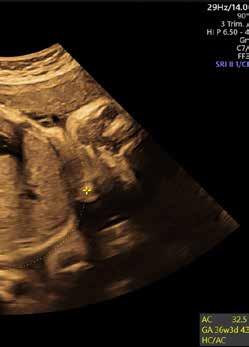

Hallo Baby

Was geschulte Augen auf Ultraschallbildern sehen.

Laien erkennen auf Ultraschallbildern nicht besonders viel. Ärztinnen und Ärzte hingegen schon. Dr. Agne Ozalinskaite, Oberärztin und Fachärztin für Frauenheilkunde und Geburtshilfe an der Klinikum Bayreuth GmbH, erklärt, was sie sehen kann beim Blick in den Babybauch.

1. Der KOPFUMFANG ist eine von drei im Ultraschall sichtbaren Messgrößen, aus denen sich das Gewicht des Kindes ermitteln lässt. Einmal von einer Kopfseite zur anderen, ein weiteres Mal von der Stirn bis in den Nacken. Dann kann man den Kopfumfang berechnen.

2. Nachvollziehbar: Auch der Bauchumfang lässt Rückschlüsse auf das Gewicht des Babys zu. Auf dem Ultraschallbild sieht die Ärztin der Bayreuther Frauenklinik die RIPPEN (a), den MAGEN (b), die LEBERVENE (c) und einen WIRBELSÄULENKÖRPER (d).

3. Die Länge des OBERSCHENKELKNOCHENS liefert den dritten Hinweis auf das Gewicht des Kindes. Und damit auch auf die Frage, ob der Entwicklungsstand zur Schwangerschaftsphase passt und ob sich eventuell ein Kaiserschnitt empfiehlt.

4. Im Ultraschall erkennt Dr. Agne Ozalinskaite auch die Lage der PLAZENTA. Die Plazenta sollte nicht am Gebärmutterhals anliegen. Denn dann wäre die Wahrscheinlichkeit groß, dass es nicht zu einer Spontangeburt kommen kann.

5. Zwei bis acht Zentimeter sind die FRUCHTWASSERTASCHEN groß. Fruchtwasser schützt vor Austrocknung und Stößen von außen, reguliert die Temperatur in der Fruchtblase und fördert unter anderem die Entwicklung der kindlichen Lunge.

6. Über diese HAUPTARTERIE wird das Baby mit Sauerstoff versorgt.

30 GESUND LEBEN

Bay r e u t h GHbm . Schwerpunkt Familie 2 3 1 b d a

31 4 5 6 b c